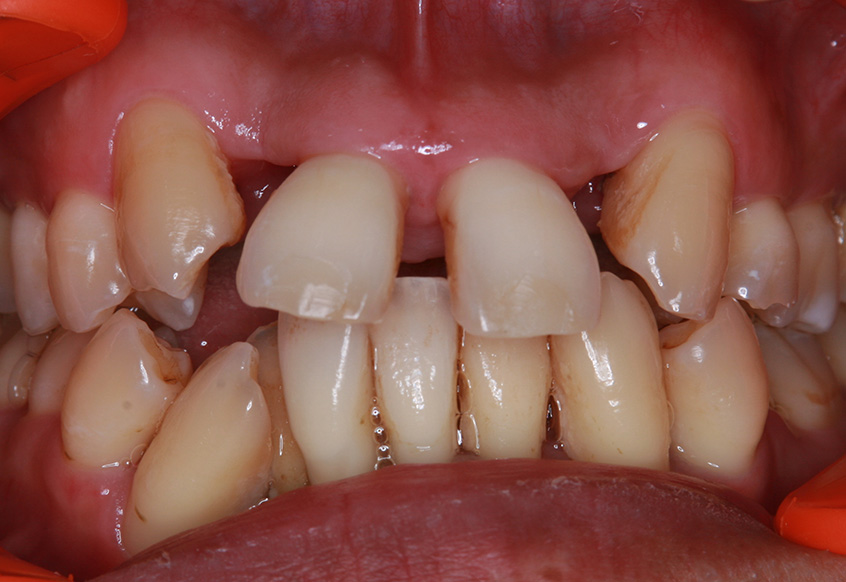

患者の方は親知らずの痛みがあり当院にお越しになりました。幼少期から歯医者が苦手で、痛みがあってもなかなか行く勇気がでなかったそうです。笑気鎮静法を併用しながら、右下の親知らずを抜歯しました。

親知らずの痛みがなくなった患者さんは、昔から歯並びが気になっていることを打ち明けてくれました。特に上の歯が少し前に出ていたり、隙間があったりしている点を治したいそうです。そこで、まず上の歯並びの矯正治療を開始しました。

| 治療内容 | 上顎側切歯を2本抜歯した後、上顎の歯にブラケットを装着し、ワイヤー、矯正用ゴムで歯の移動を行いました。その後、被せ物の治療を行って治療を終了しています。 |